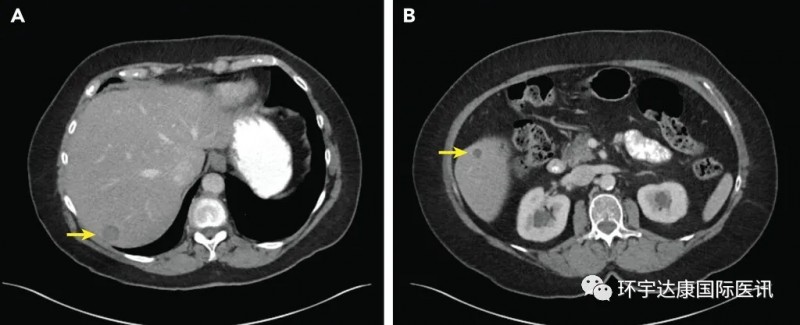

软组织肉瘤腹部隆突性皮肤纤维肉瘤新药Larotrectinib(拉罗替尼)让全身转移的患者肿瘤7天消退软组织肉瘤是间充质来源的罕见恶性肿瘤,约占成人癌症的 1%,虽然和肺癌,乳腺癌相比并不常见,但是这是一种异质性极强的复杂肿瘤,目前已知的亚型超过了100种,每一种都具有不同的临床表现。不管是罹患哪一种,晚期患者临床上的治疗方案都非常有限。手术后八年全身转移复

肉瘤靶向治疗,肉瘤靶向药物拉罗替尼挽救手术、放化疗、靶向无效陷入绝境的患者软组织肉瘤是间充质来源的罕见恶性肿瘤,约占成人癌症的 1%,虽然和肺癌,乳腺癌相比并不常见,但是这是一种异质性极强的复杂肿瘤,目前已知的亚型超过了100种,每一种都具有不同的临床表现。不管是罹患哪一种,晚期患者临床上的治疗方案都非常有限。手术,放化疗,靶向治疗后陷入绝境70岁的M女士,